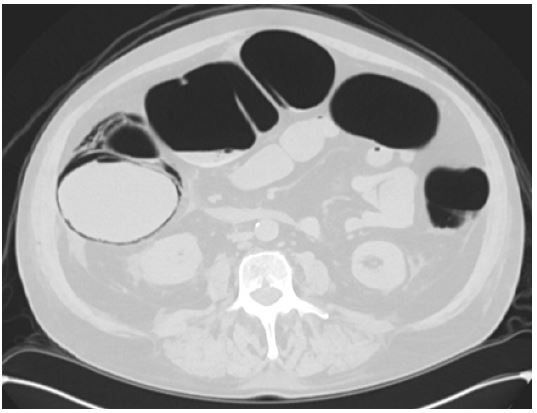

• Imaging: Chest X-ray showed hyperinflation without acute infiltrates. CT scan revealed pneumatosis coli involving the cecum and ascending colon, with no evidence of perforation or free air.

Hospital course

Figure 2: Axial view CT abdomen & plevis.